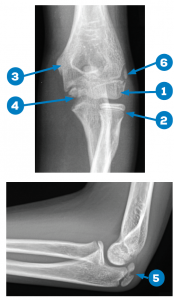

Figures 1A and 1B: Normal X-rays, 13-year-old male. 1) capitellum; 2) radial head; 3) internal (medial) epicondyle; 4) trochlea; 5) olecranon; and 6) external (lateral) epicondyle.